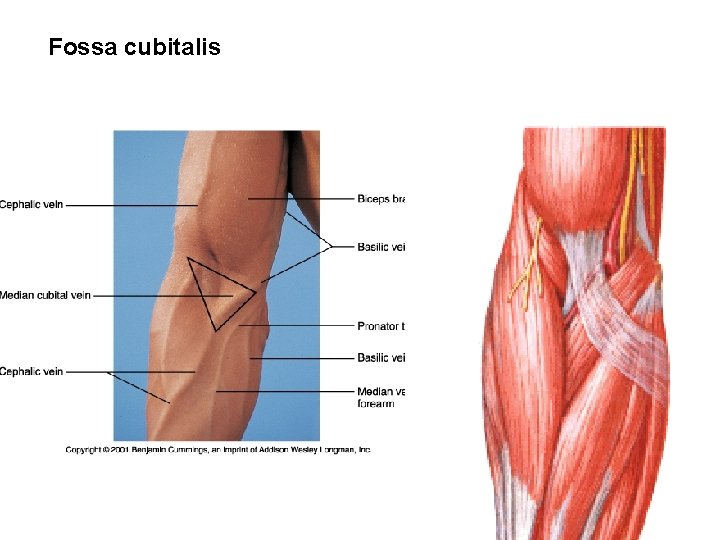

Regio cubiti et antebrachii anterior

Fossa cubitalis

N. cutaneus brachii med. N. cutaneus antebrachii med. - r. anterior - r. posterior N. cutaneus antebrachii lat. (n. musculocutaneus) V. cephalica V. basilica

V. mediana cubiti V. mediana antebrachii – v. mediana cephalica et basilica

A. brachialis - a. radialis - a. ulnaris aponeurosis m. bicipitis brachii